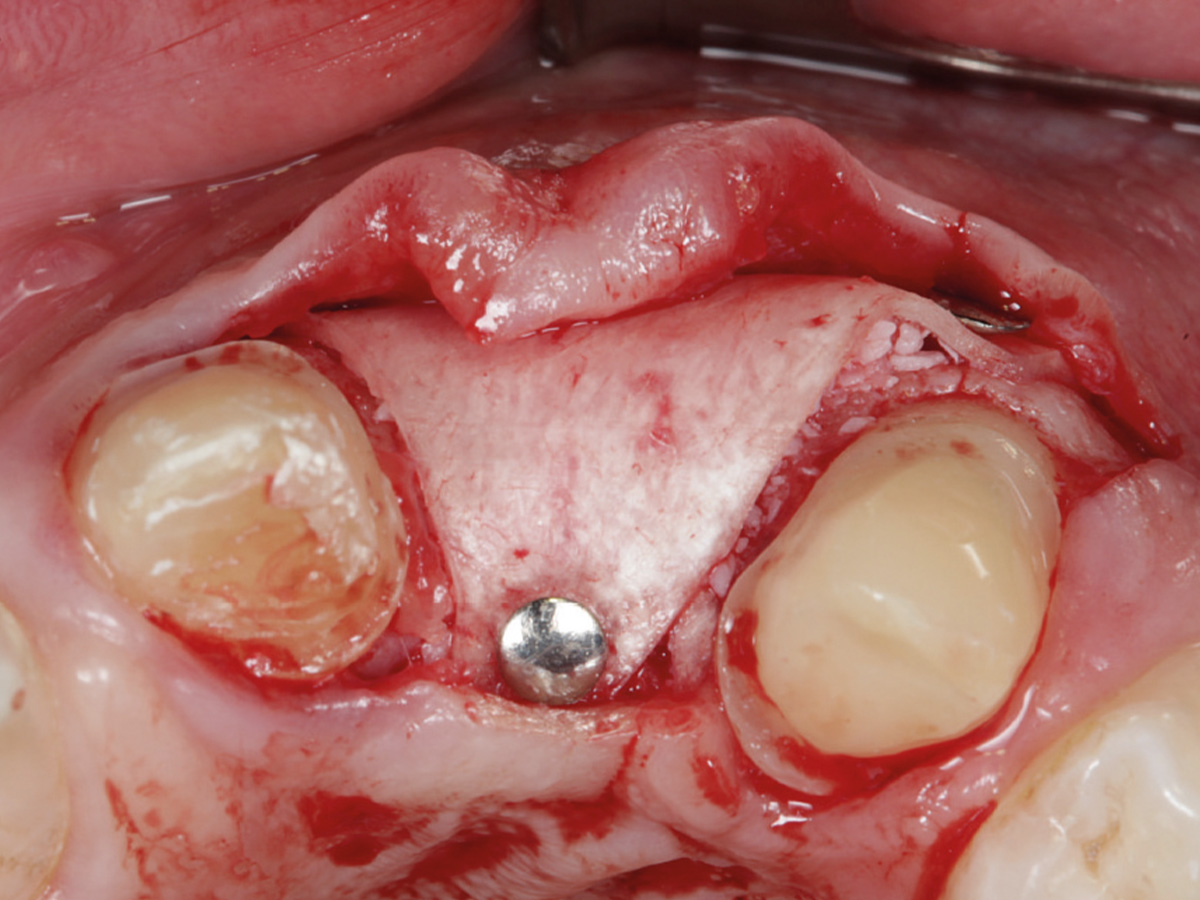

Abbildung 10

Regenerierter Bereich nach Lappenbildung. Gewebe gut durchblutet, Reste der Lamina sichtbar.